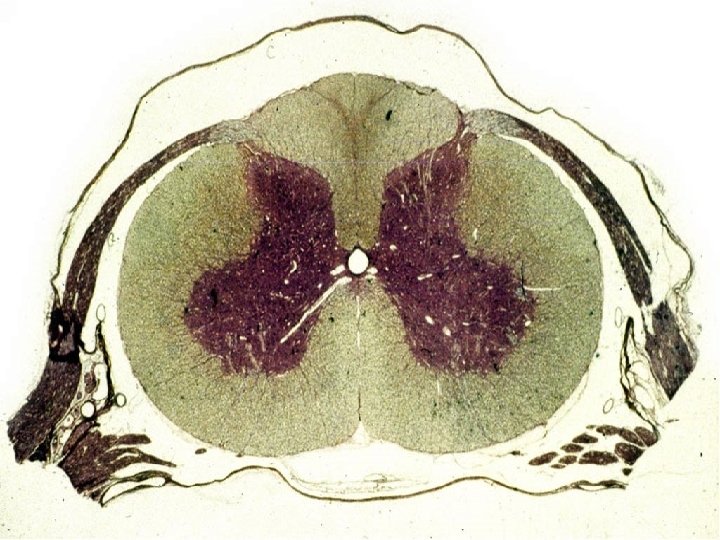

Sillon dorsal median. Substance blanche. Sillon dorso-lateral. Substance grise. Ependyme. Sillon ventro-lateral. Sillon ventral median. Vue globale d’une coupe transversale de moelle épinière.

Une coupe transversale de moelle épinière

De façon générale, la moelle épinière correspond à un cordon de système nerveux central : au niveau duquel : Ø la SG se trouve au centre, revêt un aspect en ailes de papillons C’est à son niveau que se trouvent les corps cellulaires des neurones moteurs et sensitifs

Ø la SB se trouve à la partie postérieure et ventro- latérale de la moelle C’est à son niveau que se cheminent les fibres axonales sensitives ascendantes et motrices descendantes

La moelle renferme 4 sillons, dont les caractéristiques permettent une orientation sur une coupe transversale : § un sillon ventral médian, profond § un sillon dorsal médian, petit

§ deux sillons latéraux : un dorsal et un ventral qui correspondent à l’entrée et à la sortie des racines nerveuses, respectivement La moelle comporte une commissure centrale qui correspond au canal de l’épendyme, à l’intérieur duquel chemine le liquide céphalo-rachidien (LCR)